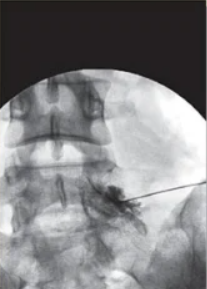

신경차단술은 허리, 목 디스크(요추 추간판 탈출증), 척추관 협착증 등으로 인한 신경성 통증을 완화하기 위해 시행하는 치료법입니다. 척추의 중심 신경에서 빠져나와 허리 통증을 유발하는 신경 가지를 영상증폭장치 (C-ARM)를 이용해 찾아내, 주사로 약물을 주입하여 통증을 완화시킵니다. 시술은 보통 국소마취로 진행, 당일 퇴원 및 활동이 가능합니다.

3) 영상 확인하며 주사 시술: C-arm(X-ray 투시장비) 또는 초음파를 이용해 신경 주변에 정확히 주사